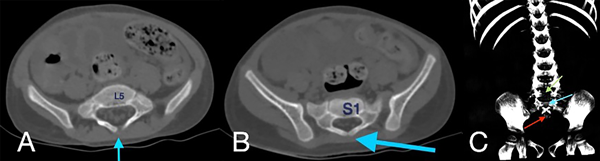

En la tomografía se evidenció presencia de S1-S2 con ausencia del resto de cuerpos sacro-coxígeos, así como hipodensidad a nivel de la médula que podría sugerir siringomielia (Figura 1). También se encontró falta de unión de algunos elementos posteriores a nivel de L5-S1 (Figura 2), lo que sugiere el diagnóstico de síndrome de regresión caudal asociado a probable siringomielia y probable vejiga neurogénica dado engrosamiento marcado de las paredes vesicales (Figura 3). Además, se encontró dilatación ureteropielocalicial de forma bilateral (Figura 4). A raíz de estos hallazgos, se solicitó una valoración por genética clínica, la cual determinó que la paciente cumple con los criterios clínicos de regresión caudal y tiene antecedentes de diabetes gestacional insulino-dependiente, lo cual es un factor de riesgo.

Figura 2. Tomografía de abdomen en ventana ósea, cortes axiales (A, B) y reconstrucción en 3D (C), donde se evidencia ausencia de unión de los elementos posteriores de L5 (flecha azul en A, flecha verde en C) y S1 (flecha azul en B y C) y ausencia de elementos sacro-coccígeos (flecha roja en C).

En este caso, se encontró una ausencia parcial sacro coxígea con preservación de S1 (Figura 1), asociada a no unión de elementos posteriores de L5 y S1 (Figura 2), siendo un síndrome de regresión caudal tipo I según Pang, asociado a alteraciones genitourinarias dadas por hidronefrosis bilateral (Figura 3) y engrosamiento de las paredes vesicales (Figura 4).